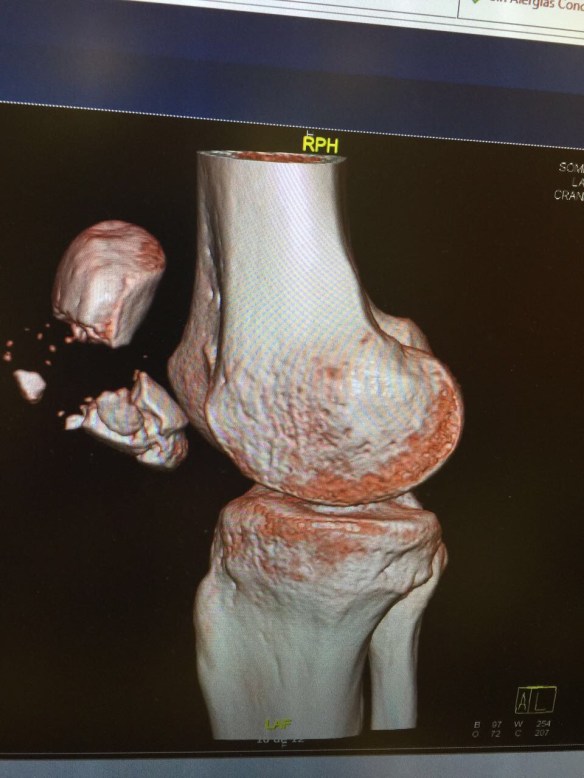

Även om jag kände att något var riktigt knasigt direkt när jag föll hade jag ändå hoppet uppe under röntgen att inget skulle vara skadat, att luxation skulle vara diagnosen och att det därför skulle gå att rätta till knäskålen så att den hamnade på rätt plats igen. Röntgenplåten talade dock sitt tydliga språk; Horisontell patellafraktur, frakturerad i huvudsakligen två delar, men med en undre del som krossats aningen mer.

Det förklarade varför jag låg där på båren och inte kunde röra benet. Förutom att givetvis smärtan var olidlig vid förflyttning fanns det inte längre någon kontakt mellan lårets muskler och smalbenet som möjliggjorde flexion. Detta är också anledningen varför en sådan här fraktur inte går att lösa på något annat sätt än med en akut operation.

Så där på plats ordnades sedan allt. Tillsammans med Liz fick jag komma upp på avdelningen i ett privat patientrum med vacker utsikt och en stor bäddsoffa som hon kunde sova i. Personalen tog direkt hand om mig och pysslade om mig på ett utomordentligt vis. Senare under kvällen stod det klart att operationen skulle äga rum under tisdagsmorgonen klockan 8 och under måndagskvällen fick jag därför träffa båda kirurgerna som tillsammans skulle genomföra operationen, få se röntgenbilderna (som de hade i sina telefoner och skickade till mig via Whatsapp), och få förklarat hur allt skulle gå till.